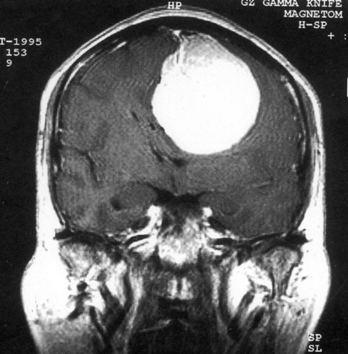

问题 病历摘要:??患者,男,40岁。发作性左下肢抽搐1年余,每次发作3~5分,每周发作1~2次。每次发作后感左下肢乏力,约半日后可自行恢复。既往身体健康。体检:神清,头顶部偏右有局限性骨性隆起(1.5×1.5cm),左鼻唇沟稍浅,伸舌居中。感觉、运动无明显异常。左浅反射减退,左下肢腱反射稍亢进,左Babinski征(-)。 脑膜瘤主要有哪些好发部位?